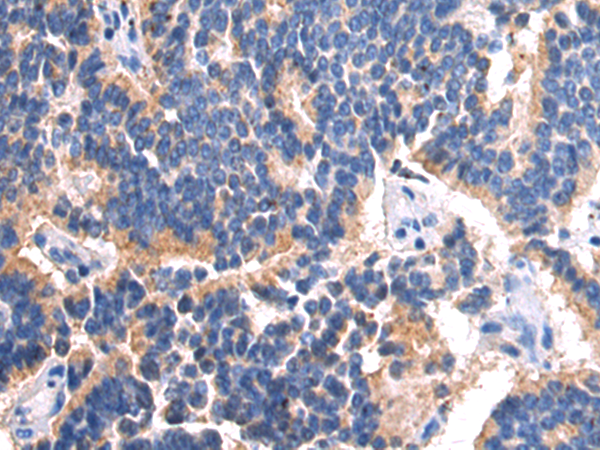

分类: 科研抗体货号: P06938别名: CPSD; CLN10; HEL-S-130P应用: WB,IHC反应种属: Human, Mouse, Rat